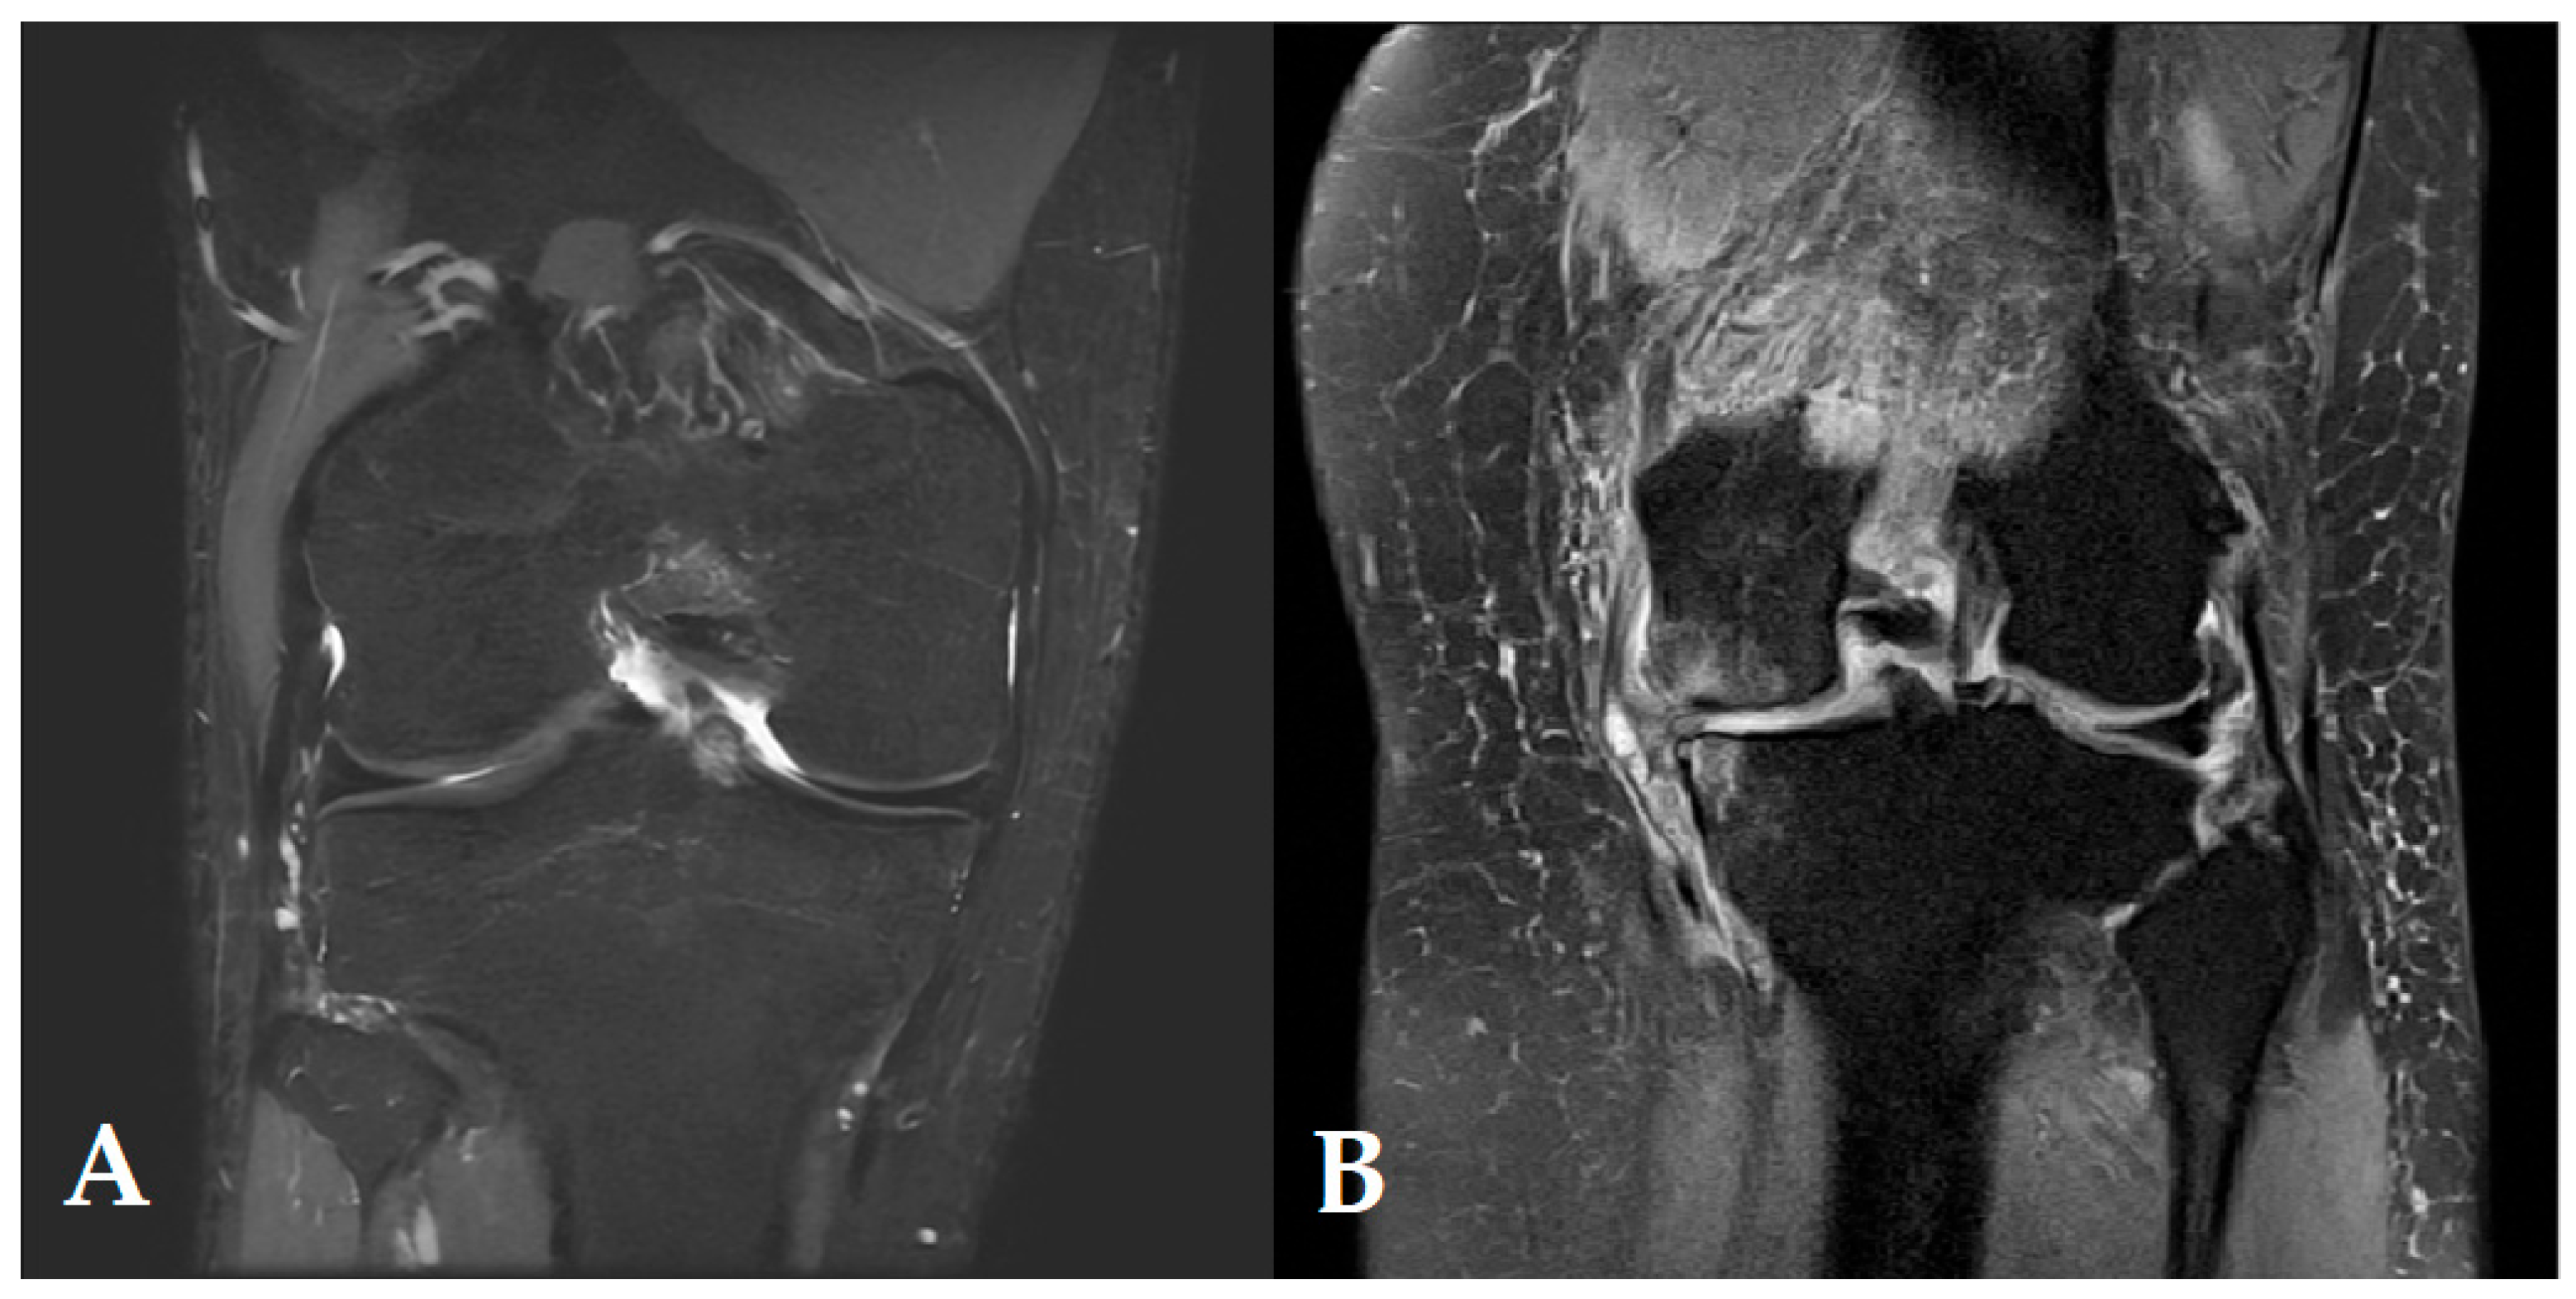

- Omoumi, P.; Mourad, C.; Ledoux, J.-B.; Hilbert, T. Morphological Assessment of Cartilage and Osteoarthritis in Clinical Practice and Research: Intermediate-Weighted Fat-Suppressed Sequences and Beyond. Skelet. Radiol. 2023, 52, 2185–2198. [Google Scholar] [CrossRef]